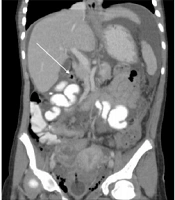

Advanced Gastric Adenocarcinoma in a 12-Year-Old Girl

Ghasem Miri-AliabadORCID*,

Leila Asgarzadeh ORCID,

Abasali NiaziORCID